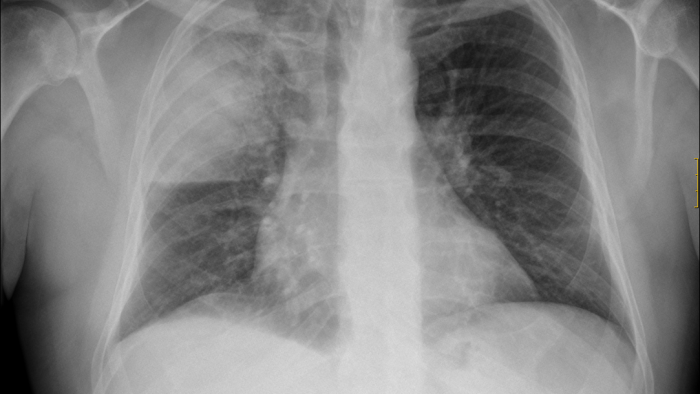

La nostra missió és restaurar la salut de tots els pacients crítics o potencialment crítics de l’hospital mitjançant sistemes avançats de monitoratge i suport vital. La nostra tasca envers els pacients la realitzem tant dins de la Unitat de Cures Intensives com fora, 24 hores al dia, tots els dies de l’any. Disposem del coneixement i dels mitjans tècnics per atendre pacients de màxima complexitat.

La Unitat de Cures Intensives (UCI) atén 1.200 pacients crítics de màxima complexitat cada any. Addicionalment, el servei dona suport a altres pacients greus que no es troben a la UCI; però que requereixen la valoració d’especialistes en medicina intensiva.

El Servei de Medicina Intensiva lidera programes transversals de l’hospital com: Codi Sèpsia, atenció a l’Aturada Cardiorespiratòria i el programa d’ECMO i col·labora molt activament en el Programa de donació i trasplantament d’òrgans.